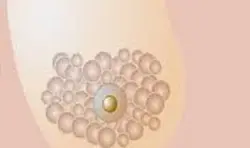

Meme Radyolojisi